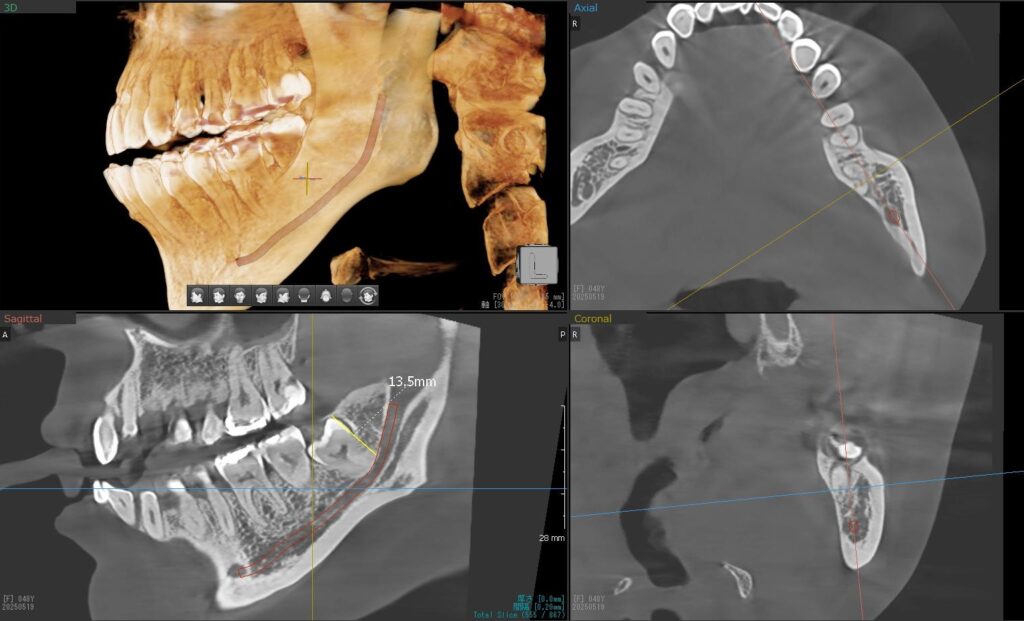

さらに、下顎の親知らずは下歯槽神経に非常に近いところに生えている場合もあるため、CTも撮影し詳しい解析を行います。

親知らずが生えている位置が、神経に近い、あるいは神経に当たっている場合は、大きな病院に紹介する場合もあります。

親知らずの根っこは下歯槽神経から近い距離にありますが、抜歯は可能との診断でした。